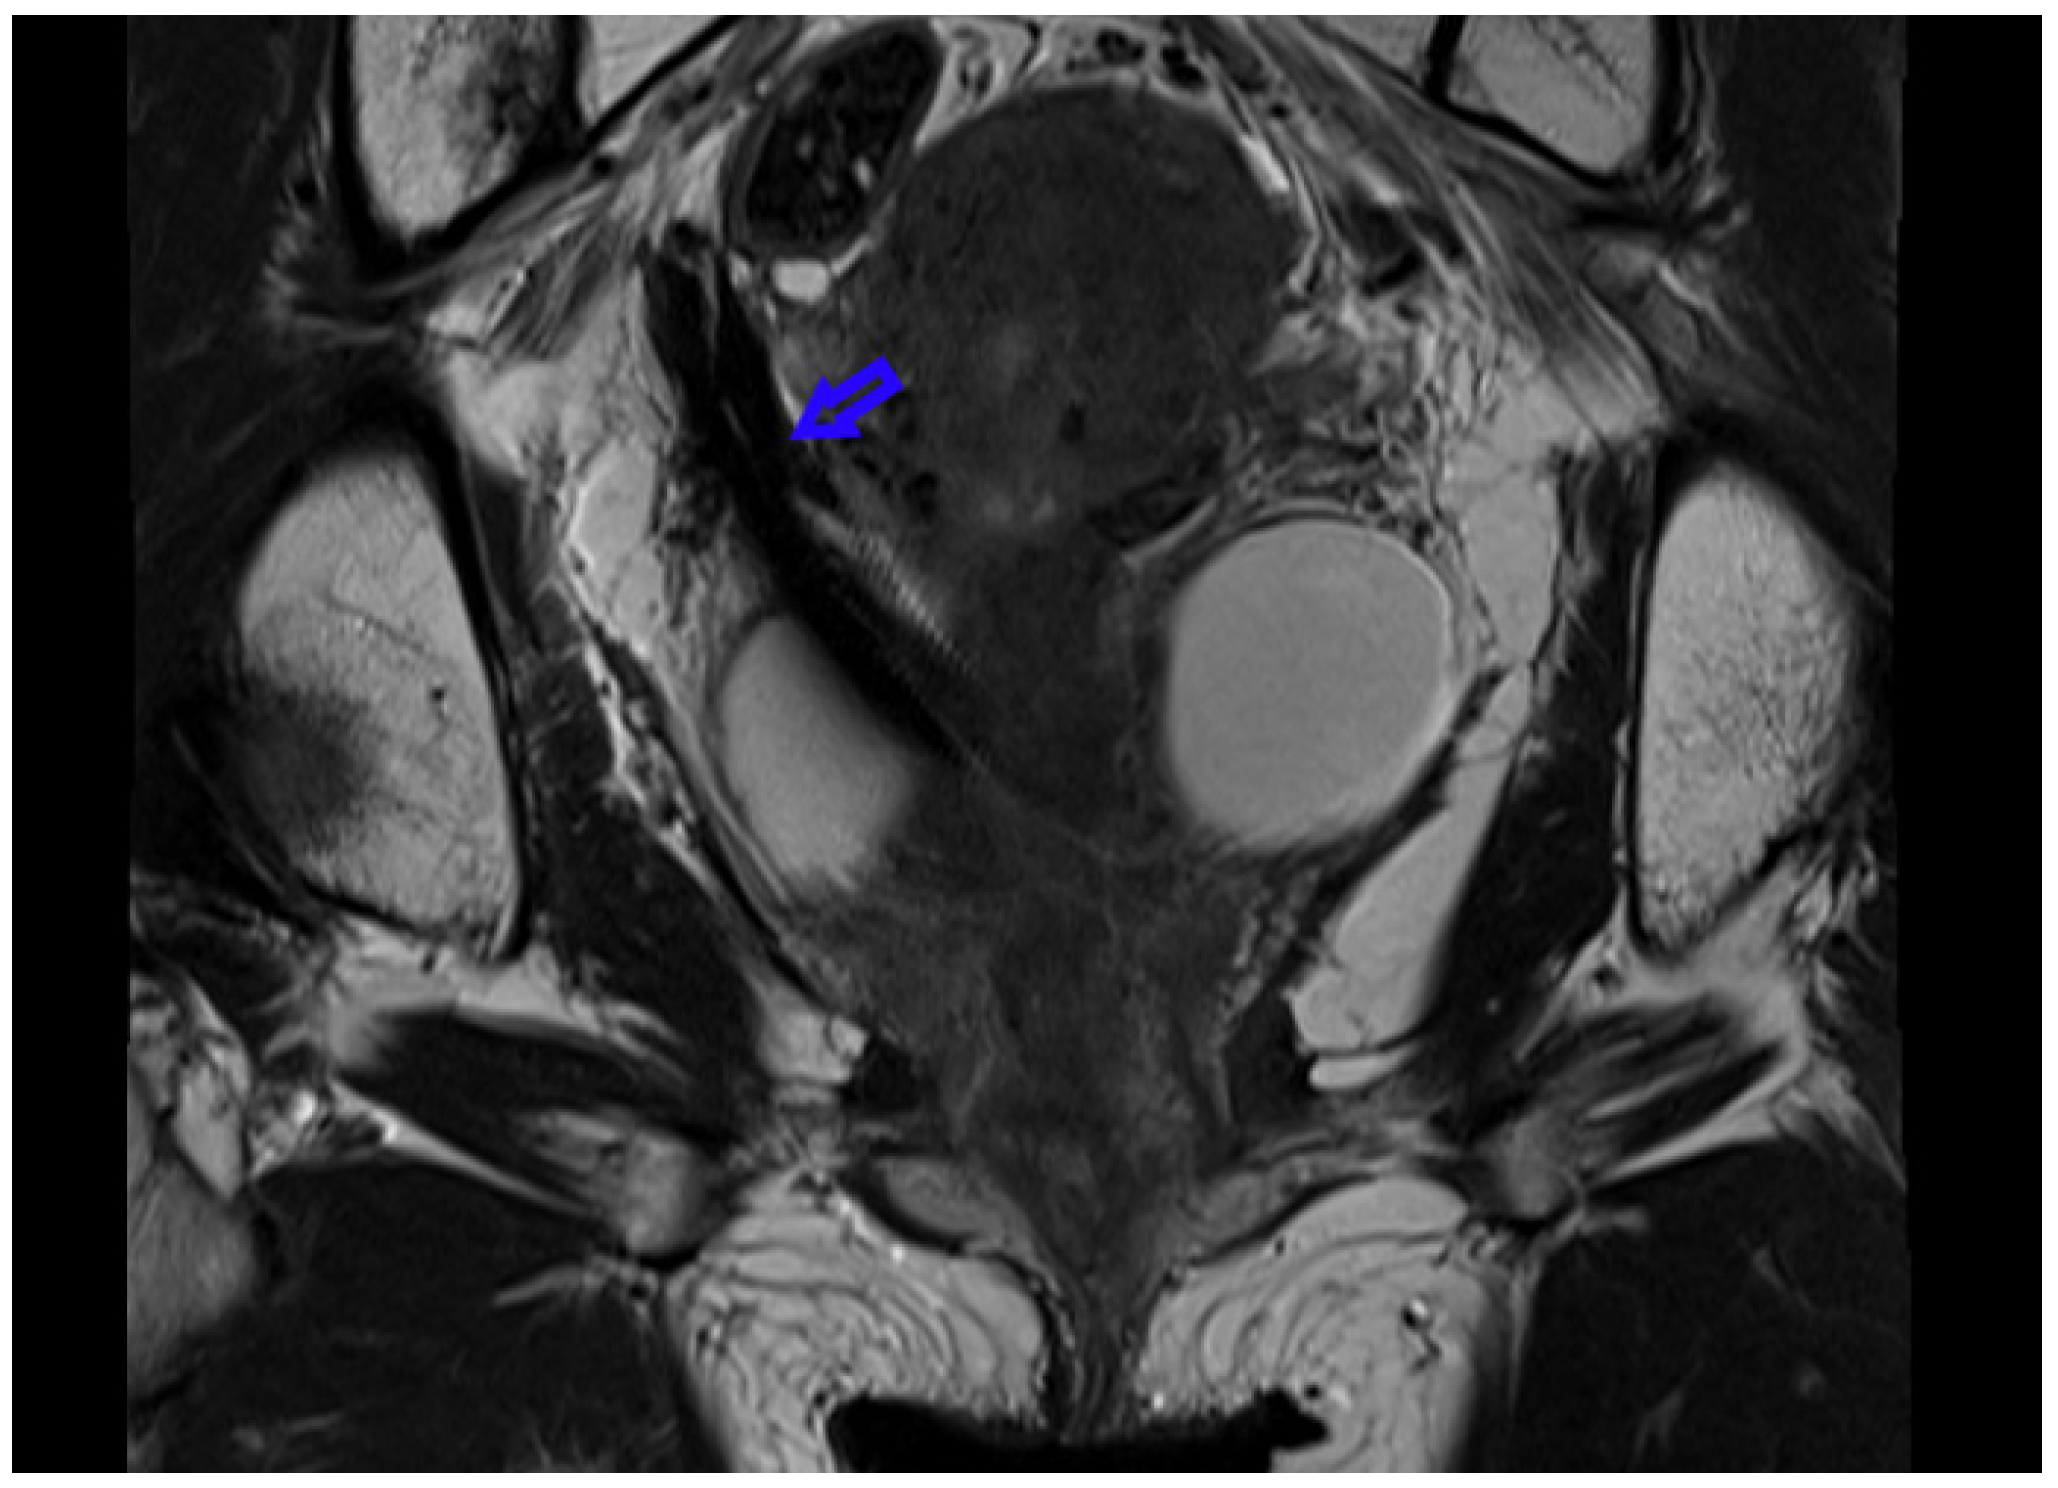

- Chin, K. Coronal magnetic resonance image of patient with Teleflex Rüsch DD Tumour Stent In Situ; Peter MacCallum Cancer Centre: Melbourne, VIC, Australia, 2019. [Google Scholar]